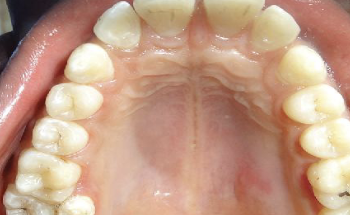

enlargement of the body and pulp chamber, most common in mand molars/ premolars, no tx necessary

taurodontism